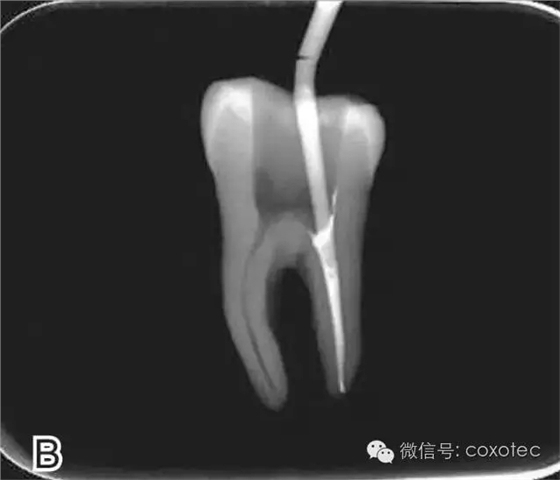

將攜熱器工作尖向根尖加熱加壓至距參照點約2 mm處,關閉加熱器,保持根向壓力,使工作尖前進到參照點處。保持加壓狀態(tài)10秒鐘(圖6)。

圖6 連續(xù)加壓,A、B.攜熱器加壓 開啟加熱器1秒鐘,迅速退出攜熱器工作尖,帶出中上段多余牙膠尖。用小號垂直加壓器向下加壓,完成根尖段的充填(圖7)。

圖7 退出攜熱器工作尖,A.垂直加壓器加壓 B.根尖段的充填完成 在完成根尖段的充填后,使用熱塑牙膠注射儀對根管中上段進行分層充填,一般分2~3次完成充填,每次充填均使用相應直徑大小的垂直加壓器進行加壓。拍片確認充填效果(圖8)。